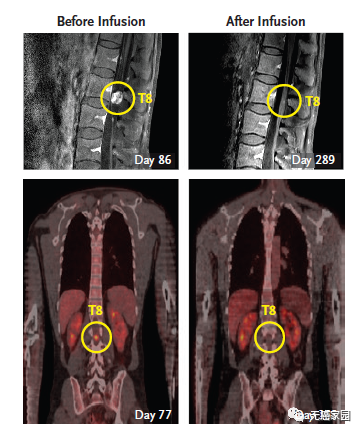

第二轮CAR-T疗法结束后,Richard Grady脊索内肿瘤出现剧烈萎缩